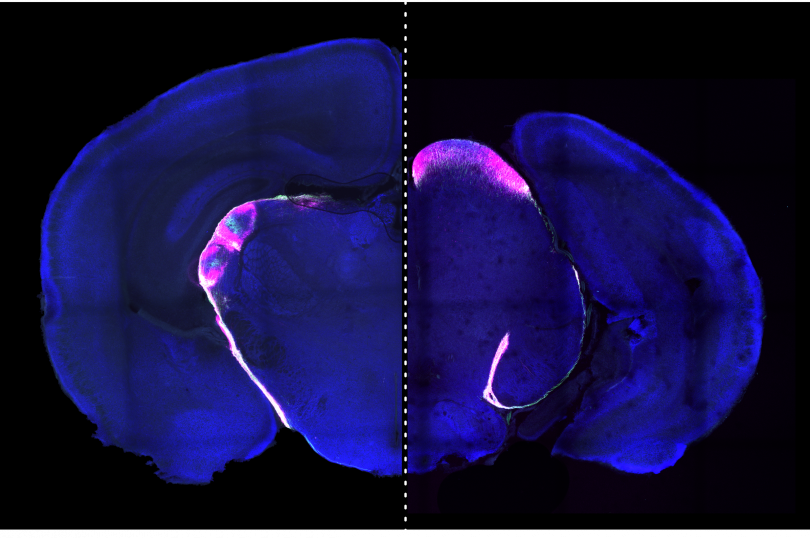

Dr. Hodes received a B.A. in Drama/Dance from Bard College and after college worked as an actor and designer in New York City. During this time, she decided a life in the arts was unsustainable and did post-baccalaureate training at Hunter College in experimental psychology. She obtained her Ph.D. from Rutgers University in the Behavioral and Systems Neuroscience division of the Psychology program where she trained in the laboratory of Dr. Tracey Shors. She went on to have 2 postdoctoral training positions, the first in Pharmacology with Dr. Irwin Lucki at the University of Pennsylvania and the second in Neuroscience with the Dr. Scott Russo at the Icahn School of Medicine at Mt. Sinai. She has received 2 NARSAD young investigator awards and is an author on over 70 publications. In 2016 she joined the faculty of the newly formed School of Neuroscience at Virginia Tech. Her research program examines sex differences in the peripheral and central immune system and how immune mechanisms interact with brain plasticity to drive behavioral differences in emotional processing of stress and mental health disorders.

The brain does not exist in a vacuum. The brain controls the body; however, the body also impacts the brain. This occurs through a variety of immune mechanisms, including cytokines and microbes produced in the periphery. When we get sick, our cells produce or suppress signals depending on the type of invasion. They tailor the environment to kill off an invading pathogen or our own injured cells. Cells then produce other signals to shut down this response and promote recovery and healing. Like physical illness, mental illness, or even stress exposure, alters immune signaling in both the body and the brain. The fundamental question driving my research is how immune pathways contribute to the pathology associated with the development of mental illness, and why are some individuals more vulnerable than others to this type of immune dysfunction?